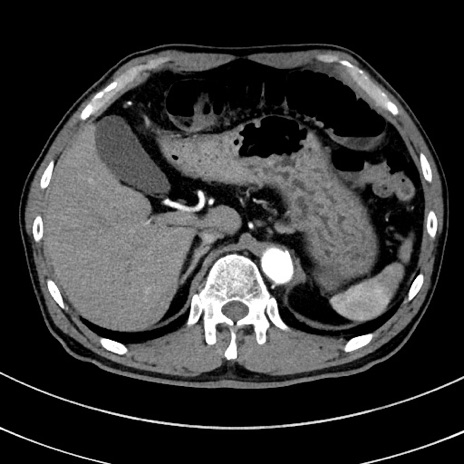

症例

冠状断像